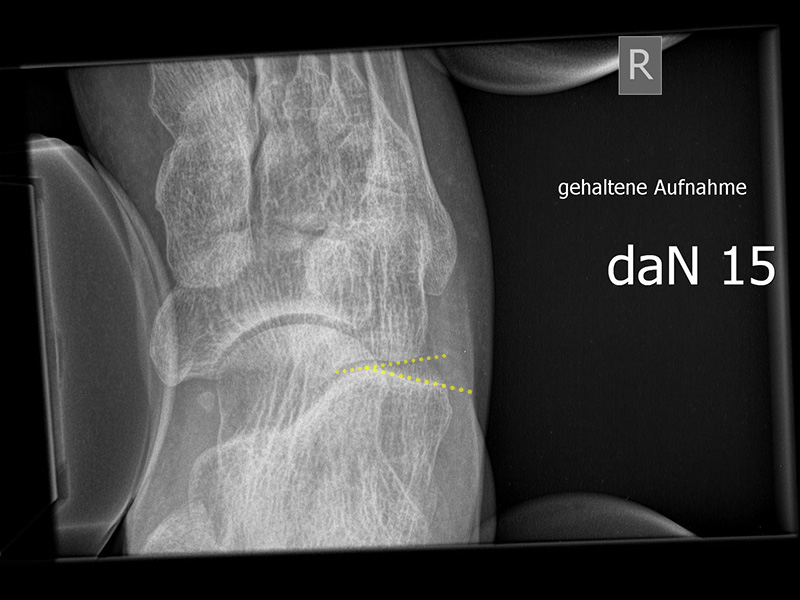

Stressaufnahme des oberen Sprunggelenks ap

Positionierung:

• Patient in Rückenlage auf dem Röntgentisch. Ferse auf der Röntgenkassette liegend (Achse des oberen Sprunggelenks parallel zur Röntgenkassette).

• Film horizontal auf dem Röntgentisch.

• Zentralstrahl mittig auf das obere Sprunggelenk fokussiert.

• Röntgenröhre 0° vertikal.

• Der Fuß liegt in der Haltevorrichtung (z.  Telos-Gerät, Scheuba-Apparat). Die Ferse wird von lateral stabilisiert, die Halterung ermöglicht ein Kippen des Rückfußes.

• Von medial wird über die Tibia ein kontrollierter Druck von bis zu 15 daN (Dekanewton, entspricht ca. 15 kg) aufgebaut.

Kennzeichen des Röntgenbildes:

• ap Abbildung des oberen Sprunggelenks.

• Beurteilung der lateralen Aufklappbarkeit.

• Subfibularer Raum mit ggf. Ossikeln einsehbar.

• Als pathologisch gelten laterale Aufklappbarkeit > 10° im Seitenvergleich oder Unterschied im Abstand zwischen der lateralen, distalen Taluskante zur Fibulagelenkfläche > 3 mm.

Besondere Bemerkungen zum Beispielbild:

• Abbildung des oberen Sprunggelenks ap.

• Laterale Aufklappbarkeit.

• Degenerative Veränderungen sichtbar mit knöchernen Anbauten am Innenknöchel.

Zur Vollansicht und zum Lesen der Bildbeschreibung bitte die Bilder anklicken.